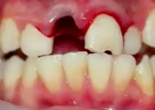

What type of injury does this look like?

Luxation